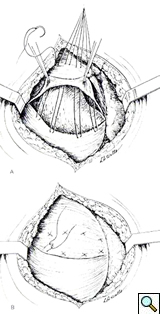

The left dome was opened anteriorly and towards the periphery following the line of insertion into the chest wall, in order to avoid injury to the major branches of the phrenic nerve. The transverse colon and the spleen were displaced inferiorly through the opened diaphragm. The colon was massively distended and was carefully reduced into the abdominal cavity. The redundancy of diaphragmatic dome was such that the posterior edge had to be trimmed removing an elliptical segment of muscle of 14 x 8 cm in size. The diaphragm was reconstructed overlapping the two edges of the opened muscle with interrupted, size O, nonabsorbable U-shaped sutures in a “double-breasted” reconstruction technique, reinforced by a second running layer (Figure 4).

The repair is most easily performed through the chest, with a lateral thoracotomy at the 7th or 8th intercostal space [4]. The strategy of surgical repair has to be adapted to each specific case. The approach through the chest makes the correction of the diaphragm technically easier. It provides exposure over the convexity of the diaphragmatic dome and allows a more precise estimation of the tension that is needed to obtain an optimal correction. The goal of surgical correction is to place the diaphragmatic leaflet in a position of maximum inspiration which relieves compression on the lung parenchyma and allows its re-expansion [4, 10, 11]. The repair of the diaphragm is accomplished by plication of the diaphragm or by imbrication. Imbrication is performed by opening the diaphragmatic dome and overlapping the two edges of the muscle (Figure 4). When the diaphragm is substantially elevated, resection of a portion of diaphragm is required, followed by reconstruction with a double breasted suturing technique.